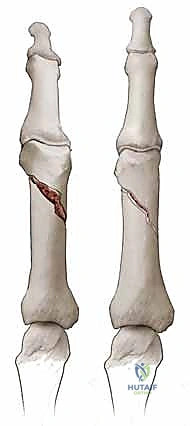

- كسور السلامية القريبة (Proximal Phalanx Fractures): غالباً ما تتخذ هذه الكسور زاوية راحية (Apex Volar Angulation). يحدث هذا لأن العضلات بين العظام (Interosseous muscles) تسحب الجزء القريب من الكسر نحو الثني، بينما تسحب آلية الباسطة الجزء البعيد نحو المد.

- كسور السلامية الوسطى (Middle Phalanx Fractures): يعتمد اتجاه الانزياح هنا على موقع الكسر بالنسبة لمكان التصاق الوتر القابض السطحي (FDS). إذا كان الكسر قريباً من الالتصاق، فإن الجزء البعيد ينثني. وإذا كان الكسر بعيداً عن الالتصاق، فإن الجزء القريب ينثني.

في الكسور المفتتة أو المعقدة، يقوم الدكتور هطيف بعمل شق جراحي دقيق (غالباً من الجانب لتجنب الأوتار الظهرية) لكشف الكسر وإعادة ترتيب الشظايا العظمية بدقة متناهية، ثم تثبيتها باستخدام:

* البراغي الساحبة (Lag Screws): تُستخدم في الكسور المائلة الطويلة أو الحلزونية لتوفير ضغط قوي بين حواف الكسر.

* الصفائح والبراغي الدقيقة (Mini-plates and Screws): تُستخدم في الكسور العرضية أو المفتتة لتوفير تثبيت صلب وقوي يسمح بحركة الإصبع في اليوم التالي للعملية.